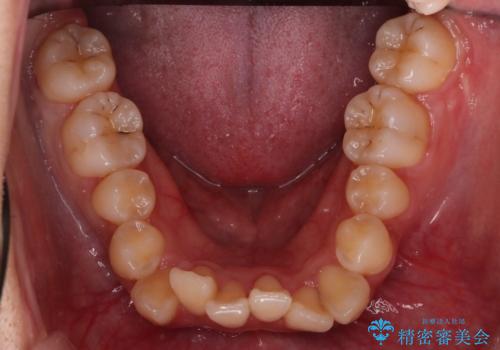

反対咬合を治したい。インビザライン

- 前歯の反対咬合を治したいことを主訴に来院されました。

インビザラインにて臼歯の遠心移動を行いながら、スペースを作り反対咬合を改善することができました。